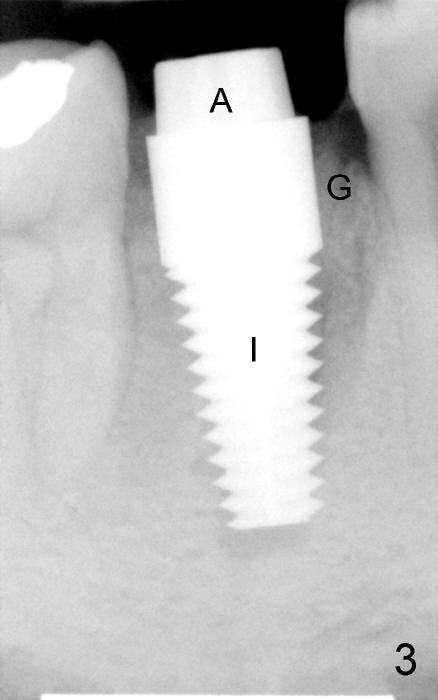

The patient returns for extraction and immediate implant after 7 days of oral Amoxicillin. There is a deep pocket mesiolingually in addition to the mesiobuccal fistula (Fig.1 <). The metal crown and then the tooth are sectioned. The crack of the mesial root is confirmed during extraction. The coronal portion of the mesiobuccal plate is defective, corresponding to the fistula. Both the mesial and distal sockets are large with a thin septum in between. Osteotomy is established at the base of the septum, slightly toward the mesial socket, as evidenced by a 5x20 mm tap in place (Fig.2). Finally, a 7x17 mm implant is placed (Fig.3 I; A: abutment; G: bone graft). The insertion torque is more than 60 Ncm.